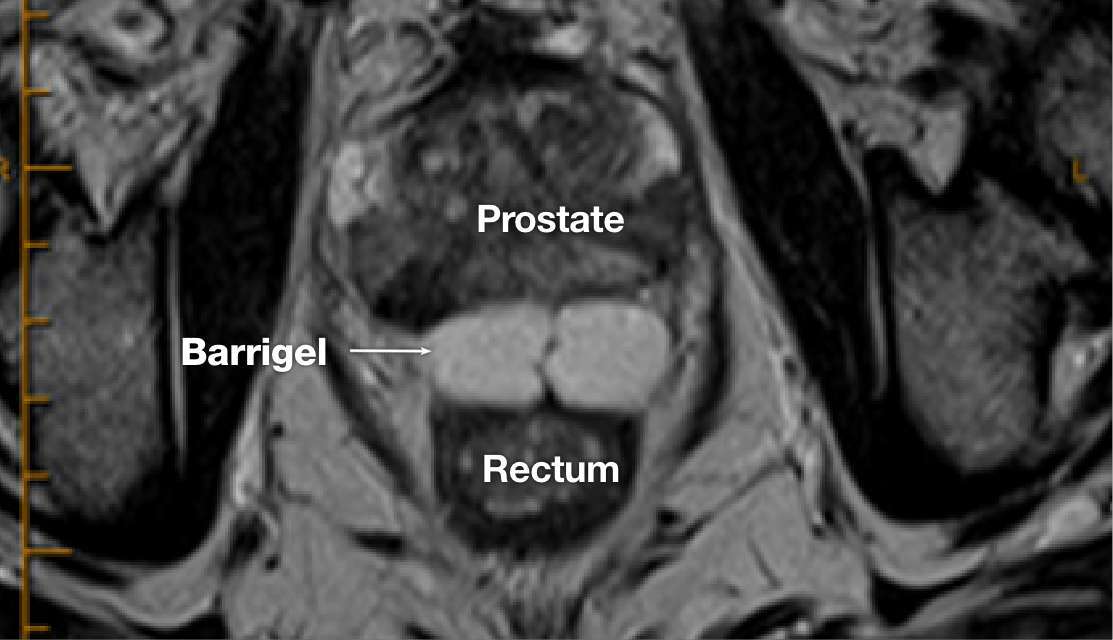

MR image courtesy of Prof Michael Chao, MBBS (Hons), FRANZCR, AFRACMA, DMedSc, Radiation Oncologist; Victoria, Australia